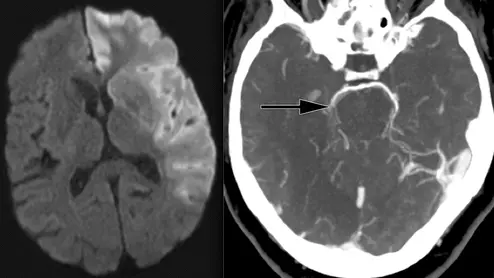

Ischemic stroke shown in CT scans. Image courtesy of RSNA

Bibb Allen, MD, FACR, chief medical officer of the American College of Radiology (ACR) Data Science Institute, explains the trend of using AI for the automated detection of stroke on computed tomography (CT) imaging and the need to include radiologists on the stroke care team.